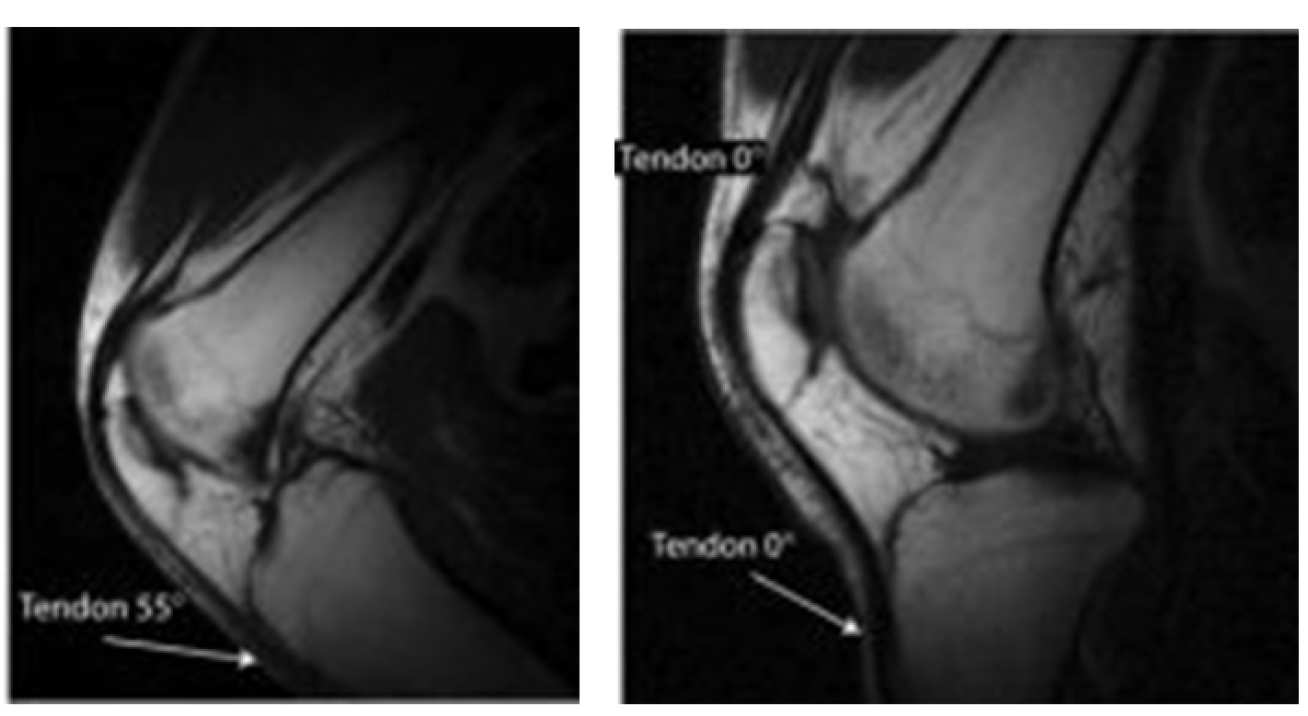

Pairs of anatomical images obtained at different angle of the main field, arrows are used to mark tissues experiencing signal changes due to the magic angle effect.

Many significant tissues containing collagen have short relaxation times which make them very hard to image using conventional MRI.

Changing the tissue orientation relative to the direction of the magnetic field can largely resolve this issue, and we have developed a magnet system which permits such changes.